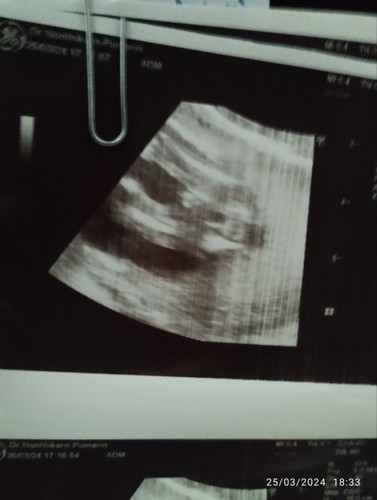

16+5วีค ช่วยบอกหน่อยคะว่า น้องผช.หรือสายสะดือ เพราะหมอบอกว่าอีกมุมดูเป็นชายอีกมุมดูเป็นหญิง อีเเม่สับสน🥹